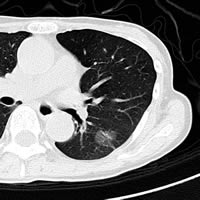

まず、肺の構造がどうなっているか、胸部X線写真(写真1)と模式図(上図)を見ながら説明しましょう。

肺には空気の通り道である気道(気管、気管支)があり、奥に入るとどんどん枝分かれして、最後はブドウの房状になった肺胞になります(下図)。肺胞は6 億個もあり、その面積は、広げるとテニスコート一面分にもなります。この広大な面積で酸素と二酸化炭素を交換するという、非常に大事な仕事をしています。

肺がんの検診方法は一般的に胸部X線写真です。たばこを吸う人の場合は、痰も調べます。通常の胸部X線写真の撮り方は、フィルムを抱くようなポーズをと り、背中側からX線をあて、1枚のフィルムに焼き付ける方法です。空気の部分は黒く、骨や水分、血管、心臓などは白く写ります。

私たち医師は、X線写真を見るとき、影がないか必死になって探します。大きさが1円玉(2礼)以下であれば、早期がんの可能性が高いからです。ワイシャ ツのボタン(1礼)くらいの影もチェックします。

しかし平面写真のため、体の前から後にあるものまですべて重なって写るし、心臓や横隔膜、骨などに重なる部分は見えません。全体の4分の1は、がんが あっても見えないのです。X線写真は、簡単に撮れて広く普及している方法ですが、肺がんの早期発見には不十分です。